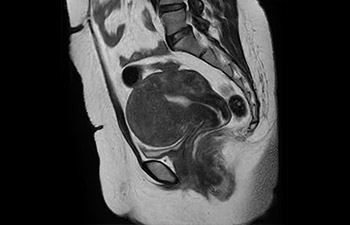

Pelvis image

Pelvis de mujer con mioma

con Compressed SENSE